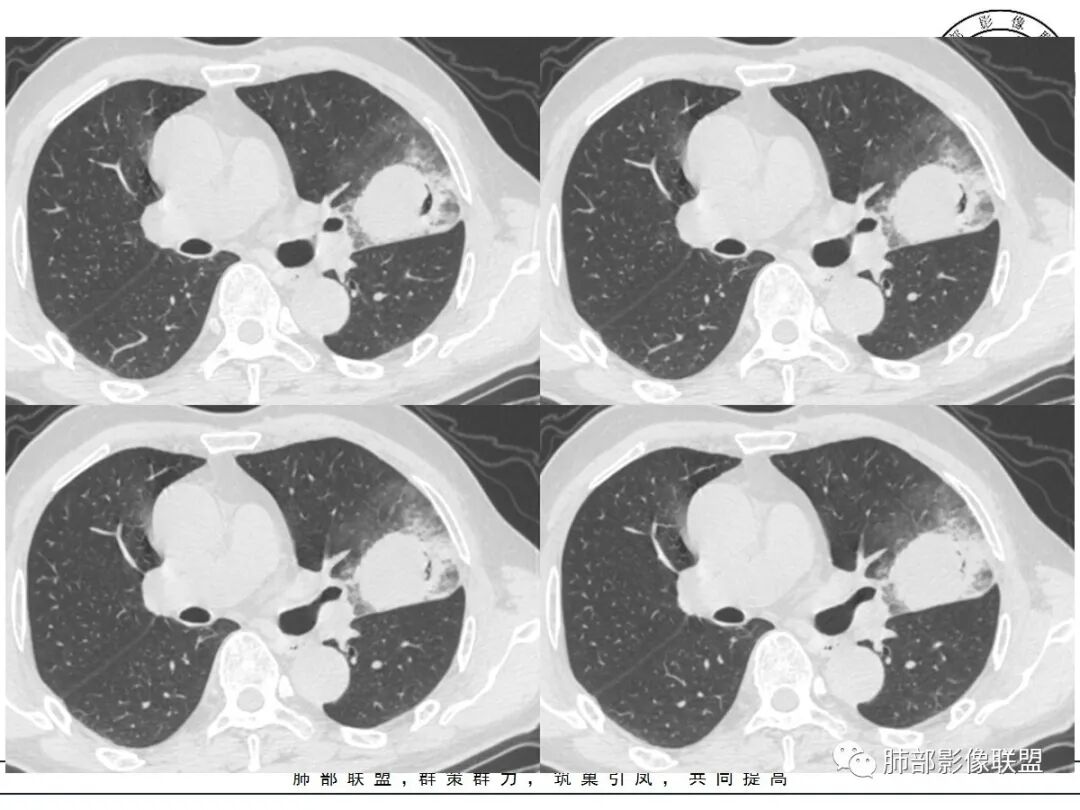

@小赵 这个不一定是粘液,很可能还是周围癌性浸润。看术前复查,原磨玻璃区呈明显小叶间隔增厚改变了。说明还是癌性淋巴浸润。

@温附一影像科,傅钢泽 应该是STA(气腔播散)加癌性淋巴管炎。

支气管稍扩张→有张力,GG0边缘清楚,局部有小叶间隔阻挡。

反思,恶性膨隆,远端空洞,强化坏死不均,里面血管似乎也是增粗,边界不清,似乎有侵犯。坏死还是边界不清。

1、团片状,实行密度区外观整体圆顿,位于上叶尖后段与下舌段区间。局部膨隆,但未见分叶,肿瘤多见。

2、偏心空腔病灶,气腔略呈新月形,壁不规则,腔内结节相对密实,明显强化且不均,支持新生物而非曲菌球等。炎性空洞多有强化环。

3、病变强化较明显,其内隐约显示多发小斑片状无强化灶,可疑边界不清小灶坏死区。病灶内血管影浅淡、模糊不规则。

4、支气管改变:上舌段支气管远段延入部分稍示僵硬。尖后段见分支支气管阻塞,恶性多见。

5、周围磨玻璃,3个月后逐渐转为密实,应符合当初附壁生长为主,且逐渐向实体成分转换。

6、病变长轴平行且受限于胸膜,外围大内带小,符合外朝内发展病变。“腔内结节状明显强化”加之支气管改变有力支持新生物诊断。如此大范围边界不清的磨玻璃影让人浮想联翩。如此大范围病灶,肺门纵隔未见肿大淋巴结也让人意外。